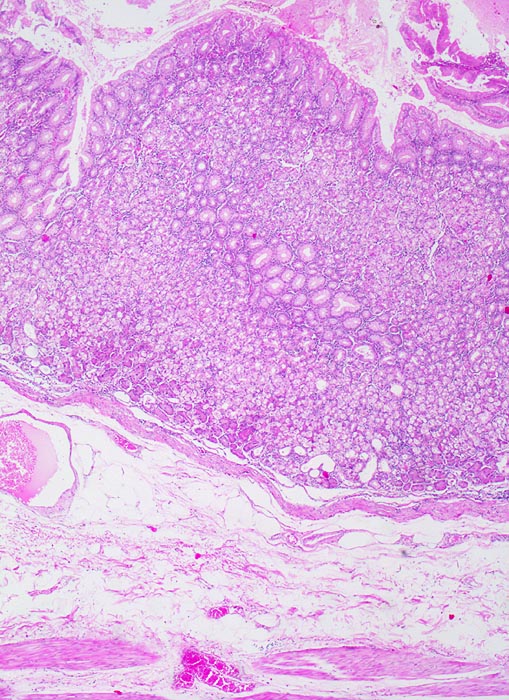

Die ersten beiden Typen entsprechen histologisch meist einem intestinalen Typ nach Lauren (> 1342). Diese Tumoren sind scharf begrenzt, bilden tubuläre oder papilläre Strukturen wie die Dickdarmkarzinome, sind meist assoziiert mit bekannten umweltbedingten Risikofaktoren und haben eine bessere Prognose.

Adenokarzinome können tubuläre, papilläre, muzinöse, siegelringzellige und undifferenzierte Anteile aufweisen, wobei die beiden letzteren besonders aggressive Tumoren darstellen.